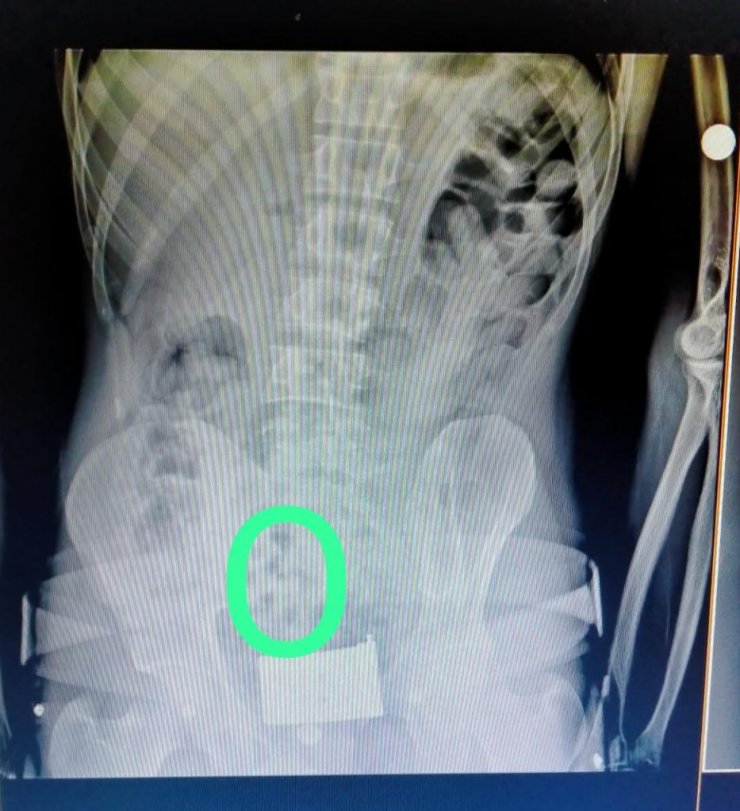

İl Emniyet Müdürlüğü Narkotik Suçlarla Mücadele Şube Müdürlüğü ekipleri, Erzincan- Erzurum yolunda aracı durdurdu. Polis, İran'dan Türkiye'ye giriş yapan araçtaki 2 kişiden şüphelenince muayene için hastaneye götürdü ve röntgen çekildi. İran uyruklu kişilerin midesinde kapsüller olduğu görüldü. Hastanede yapılan işlem sonrası 2 şüphelinin midesinden 64 kapsül halinde 558,83 gram eroin çıkarıldı. Emniyetteki sorguları tamamlanan Ali F. ile Saman G., sevk edildiği adliyede çıkarıldığı hakimlikçe tutuklandı.